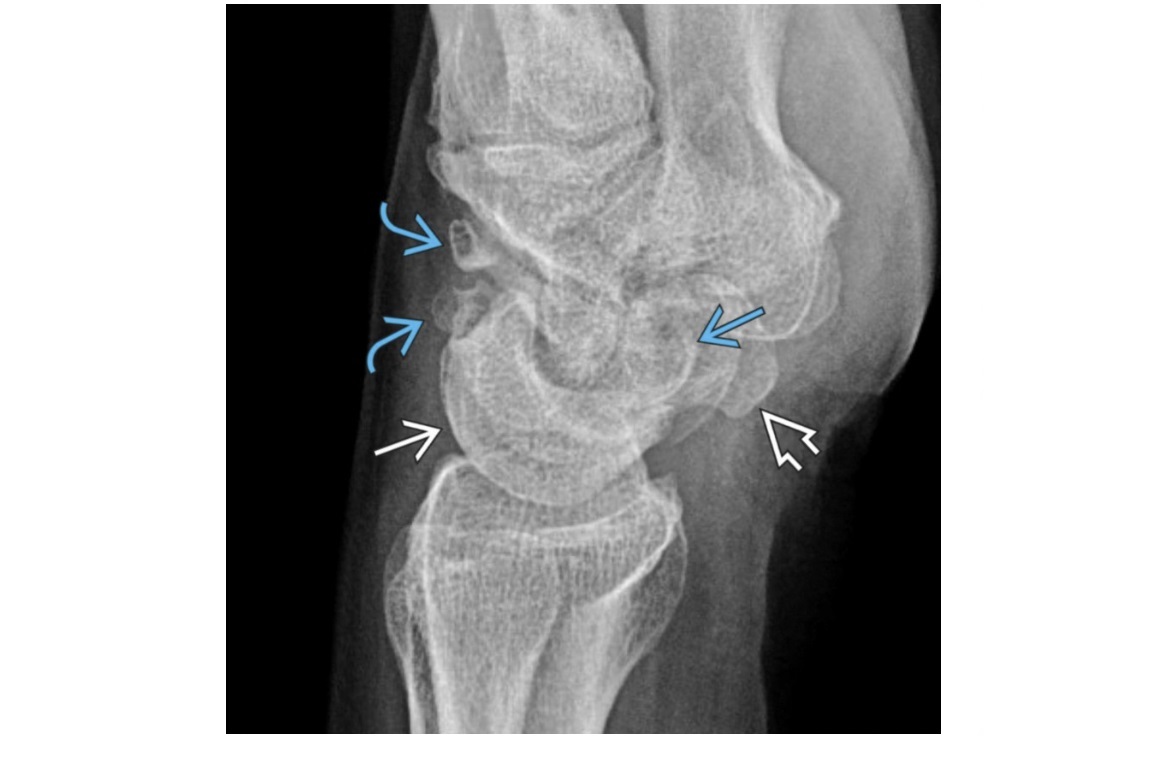

problem with the development of the ulnar side of the distal end of the radius. The distal radioulnar joint subluxes and the ulna displaces dorsally. proximal carpus is V-shaped

Madelung deformity growth failure of the distal radius, by comparison the ulna appears lengthened (Positive ulnar variance). appearance is of a V-shape to the radioulnarcarpal joint with angles of <120 considered characteristic. Mnemonic = DIGIT D = Dysplastic - Ollier disease, osteochondromatosis, achondroplasia, mucopolysaccharidoses, diaphyseal aclasis I = Idiopathic G = Genetic - Autosomal dominant. 50% of patients have bilateral deformities. **Most common association is Turner syndrome** I = Infection T = Post-Traumatic